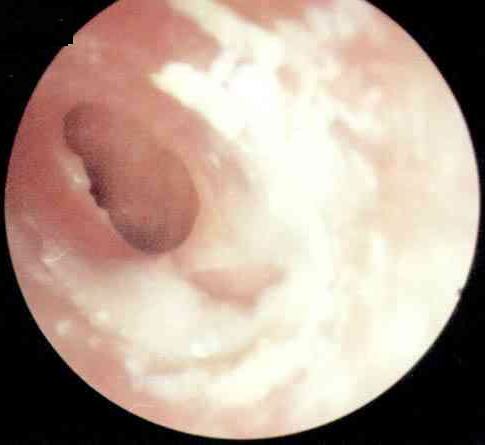

化脓性中耳炎病理图

又称坏死型或肉芽型,多由急性坏死型中耳炎迁延而来。组织破坏较广泛,病变深达骨质,听小骨、鼓窦周围组织可发生坏死;粘膜上皮破坏后,局部有肉芽组织或息肉形成。此型特点:耳流脓多为持续性,脓性间有血丝,常有臭味。鼓膜紧张部大穿孔可累及鼓环或边缘性穿孔。鼓室内有肉芽或息肉,并可经穿孔突于外耳道。传导性聋较重。乳突X线摄片为硬化型或板障型,伴有骨质缺损破坏。